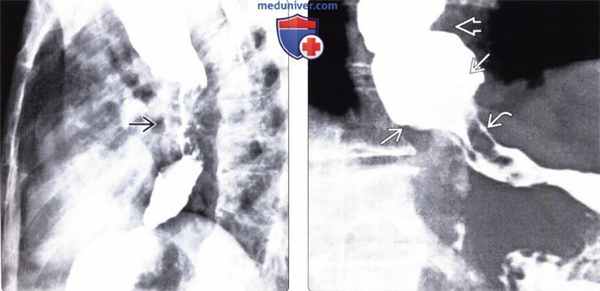

(Слева) На рентгенограмме пищевода, выполненной во время рентгеноскопии перед оперативным вмешательством — миотомией по Геллеру, определяются типичные признаки ахалазии в виде «птичьего клюва» в области дистального отдела пищевода, значительное расширение просвета вышележащих отделов пищевода, а также отсутствие перистальтических сокращений.

(Справа) На рентгенограмме пищевода у этого же пациента после миотомии по Геллеру определяется значительное уменьшение степени дилятации пищевода. Пищевод легко опорожняется в положении пациента стоя, его содержимое проходит в желудок под влиянием силы тяжести, т. к. перистальтика пищевода все еще отсутствует.в) Дифференциальная диагностика ахалазии кардиального отдела пищевода:

(Слева) На рентгенограмме пищевода определяются типичные признаки ахалазии, а также множественные бляшки неправильной формы, свидетельствующие о кандидозном эзофагите.

(Справа) На рентгенограмме пищевода со взвесью сульфата бария в вертикальном положении, полученной у женщины 78 лет с дисфагией, визуализируется не прошедшая в желудок пища и жидкость Ев на фоне выраженной дилятации просвета пищевода. Визуализируются также непропульсивные третичные сокращения пищевода. Этот пример является иллюстрацией гипертонической ахалазии, при которой стенка пищевода сокращается, но эти сокращения не являются эффективными. При манометрии была подтверждена ахалазия.г) Патология:

(Слева) На рентгенограмме пищевода, выполненной пациенту с длительно существующей ахалазией, визуализируется объемное образование, неравномерно суживающее просвет пищевода в виде «огрызка яблока». Позже было подтверждено, что образование представляет собой плоскоклеточный рак пищевода.

(Справа) На рентгенограмме определяется расширение просвета пищевода, а также третичные сокращения — изменения, напоминающие таковые при ахалазии. Резкое сужение просвета пищевода с «подрытыми» краями и наличие узловидно утолщенных складок слизистой оболочки позволяет заподозрить рак желудка, обусловливающий наличие признаков псевдоахалазии.д) Клинические особенности: